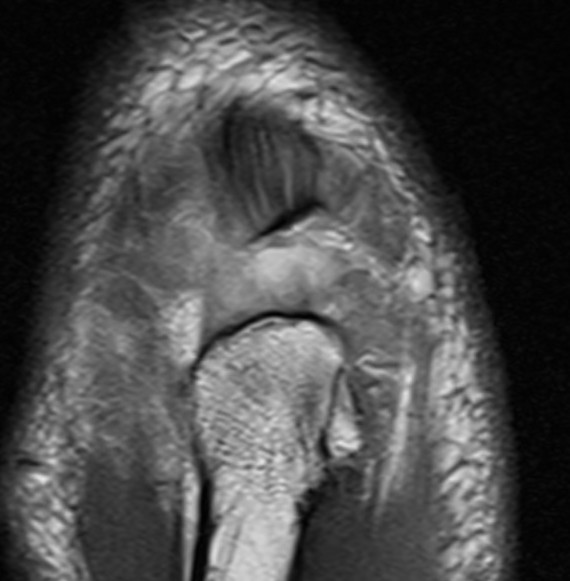

MRI

- suture bridge / double row

- two proximal suture anchors

- distal knotless anchors / tranosseous fixation

- restore triceps footprint

Anatomic triceps repair with proximal suture anchors and double row transosseous repair